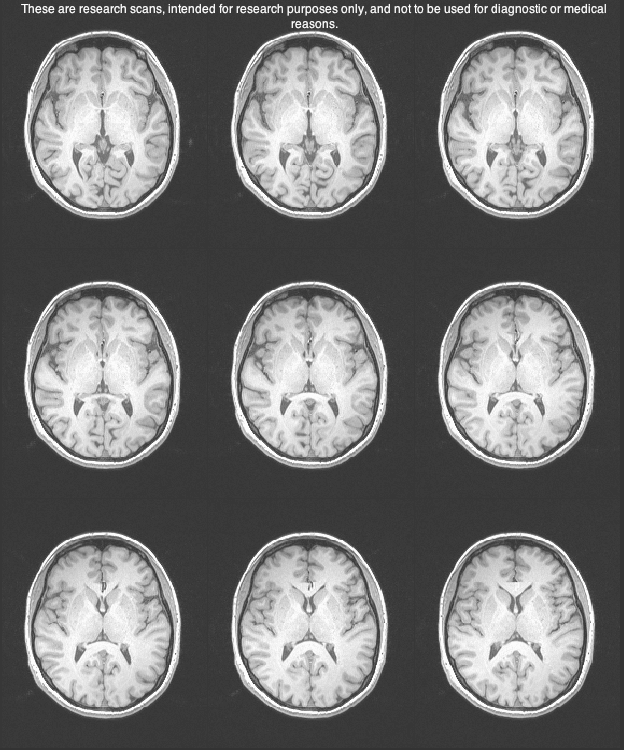

Two days ago they did a test on my memory and how the brain stores information. They sat me at a computer and they would flash a word at me like ‘giraffe’. I would then as quickly as possible determine whether it is living or non living using the buttons strapped to my fingers. From there I had to do this really quick mathematical addition in my head with numbers flashing up on the screen at me and then decide whether the number they showed me at the end was the correct answer to the addition. From there, you then have to recall the word. They do all of this while you are strapped into an MRI machine measuring the different activities of your brain in doing the sums and the recall. The hypothesis that they are testing is whether or not the long term memory is more effective when you focus more on the word that you have to remember or when you are busy with a distractor task, ie. the maths sums. Strangely enough, they have been finding that the words that you do the distractor task with are more likely to be remembered long term as the way that these words are processed in the brain is different. Really interesting study. Probably why I did so well at university studying with the TV on, the radio on, talking on the phone and trying to read at the same time! Me being as competitive as I am too, I had to try and beat my own scores and the scores of others with the decision making and the maths. I was killing it to a point. 85-90% 🙂 Not bad when the average is around 60-70% for the maths! Looks like all of the learning books and the brain training games are paying off!

Of the most lucrative and probably most uncomfortable of the medical tests that I have done was the PET scan. After doing a two hour screening of different IQ type tests with shapes and logic and a psychological evaluation, they sent me off to do the scan. They put me in a hospital gown, laid me onto the table and then started to put in the arterial line in my left wrist. Luckily they hit it the first time so it wasn’t too bad in the healing process. They put the radiotracer into my right arm and then I pretty much laid in the machine for 2 hours while they scanned my brain to see where the radiotracer was collecting and if it was more concentrated in specific areas of the brain or not for a specific enzyme that they are attributing to swelling in the brain that is related to depression.

They took different blood samples from my wrist throughout the experiment to look at the concentration of the radiotracer in my blood and I have to say it wasn’t the most comfortable of situations. What I didn’t realize was that they actually put a plaster cast thing over your face to lock it into place for the scan so that your head doesn’t move. So here I am, head locked in in a plaster cast, needles sticking out of my arms, the most ADHD I have ever been and all I wanted to do was go for a dance or move around or do something! The two hours were finally up, I had my arterial line out, went for a 20 minute MRI and took my cash for the day. More money than I would have earned in the space of a week and a half working for minimum wage in Toronto on half a day of being a guinea pig for the advancement of science. I will most certainly take that.